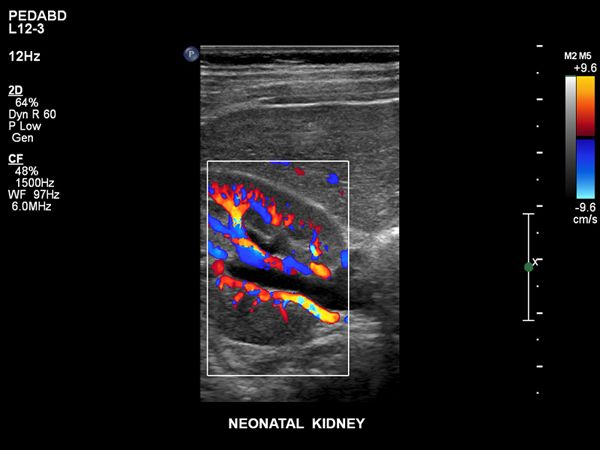

Philips ist bekannt für seine Expertise in Sachen Bildgebungstechnologien und hat mit nSIGHT eine revolutionäre neue Bildgebungstechnologie und eine völlig neue Methode zur Erstellung von Ultraschallbildern entwickelt, die folgende Möglichkeiten bietet:

- Besonders detaillierte Ultraschallbilder und eine außergewöhnliche zeitliche Auflösung

- Fähigkeit, Gewebehomogenität auf einer ganz neuen Ebene zu erkennen, ohne die Notwendigkeit der kritischen übertragenen Fokuszonenplatzierung

- Außergewöhnliche Penetration bei höheren Frequenzen für eine hervorragende Bildgebung bei schwierigen Patienten